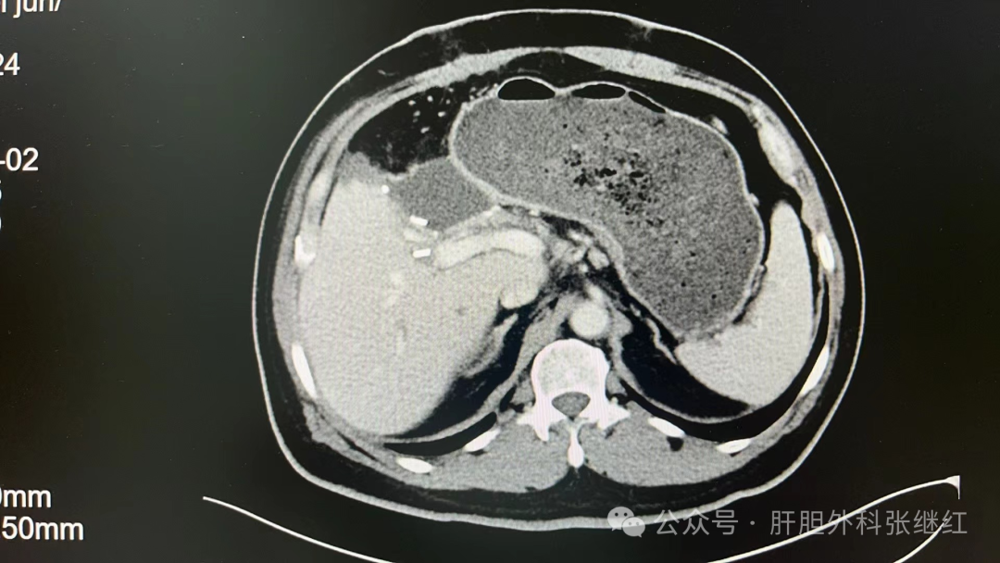

该患者是佛山复星禅诚医院肝胆胰外科病例,张继红医生有幸参加了术前多学科会诊和手术。1年前,一男性56岁病人,经CT、MR等影像学检查和病理活检确诊为胆管细胞癌,瘤体巨大,长径超过10厘米,且伴门静脉左支癌栓形成和多发腹腔淋巴结转移,经多学科会诊后决定应用吉西他滨和奥沙利铂化疗联合PD-L1单抗(度伐利尤单抗)免疫治疗进行转化治疗后再手术切除。经上述化疗联合免疫治疗五个疗程(每次均为单次给药,间隔时间21天)治疗后肿瘤明显缩小,直径约5厘米,淋巴结病灶也有所减少或缩小,达到了影像学部分缓解和手术切除的标准,经多学科会诊后决定行扩大左半肝切除及区域淋巴结清扫术,术后再行辅助治疗。本为腹腔镜手术,术中见左肝肿瘤萎缩明显,肿瘤压迫右侧肝蒂,肝门部及肝总动脉周围未见明显肿大淋巴结,肝门部粘连严重,仅清扫12a、12b、7-9组淋巴结所在区域脂肪淋巴组织,解剖离断左肝动脉、门静脉左支及左肝管,发现肿瘤基本位于缺血范围内,超声引导下在缺血线和S5段肿瘤外侧画切肝线,拟切除包括胆囊的S5段和左半肝,15+5min模式间歇性阻断肝门,沿预切线离断肝实质,达右肝蒂时发现肿瘤紧贴右肝蒂,为避免右肝蒂损伤,中转开腹完成整块切除包括胆囊的S5段及左半肝。手术后病理证实肿瘤100%坏死,清扫淋巴结亦未发现肿瘤细胞,达到病理学完全缓解(pCR)。术后早期肝断面少许积液,经引流后积液消失。目前病人状态良好,已无瘤生存半年余。

3c1aaa1f38dc4e9d8c8137c4a424212b.jpg  转化治疗后CT